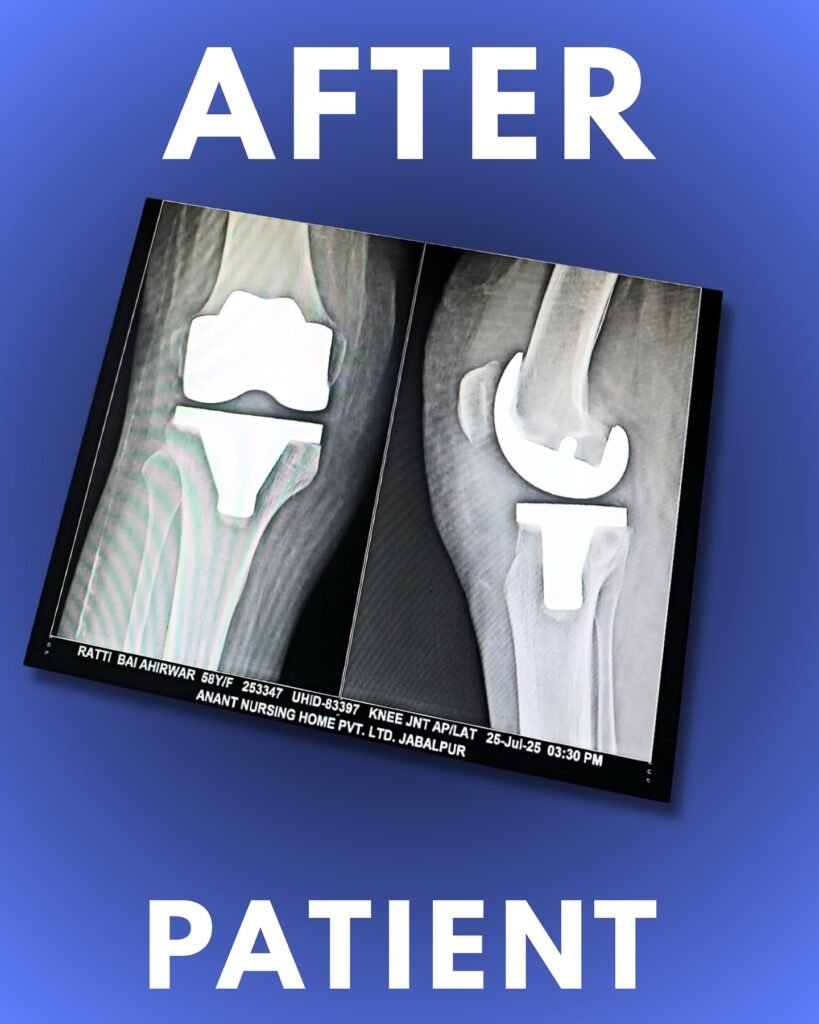

The damaged cartilage and a small portion of bone from the femur and tibia are carefully removed to create a smooth base for the implant. This step ensures accurate alignment and stability of the artificial joint.

• High-quality metal components are placed on the prepared bone surfaces. These implants recreate the natural shape of the joint and may be cemented or press-fitted to promote strong fixation.

The undersurface of the kneecap (patella) is often resurfaced with a smooth plastic button, allowing friction-free movement and improving knee function after surgery.

A durable medical-grade plastic spacer is inserted between the metal parts to create a smooth gliding surface. This allows the joint to bend and move naturally without pain.

With his advanced surgical expertise, Dr. Nachiket Pansey ensures exceptional outcomes, faster recovery, and lasting comfort for patients seeking knee replacement surgery in Jabalpur. His dedication and precision make him the most trusted orthopedic doctor in Jabalpur for comprehensive knee and joint care.